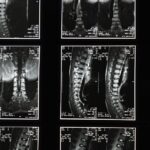

La décompression neurovertébrale est une technique innovante qui nécessite une formation spécialisée pour les professionnels de santé. Cette méthode, utilisée principalement pour traiter des pathologies vertébrales telles que les hernies discales et les douleurs chroniques du dos, nécessite des connaissances approfondies en anatomie, en biomécanique et en diagnostic médical.

La décompression neurovertébrale est une méthode thérapeutique novatrice visant à traiter diverses douleurs spinales, notamment celles liées aux hernies discales et aux douleurs lombaires chroniques. Pour garantir une pratique sécurisée et efficace, il est essentiel que les professionnels de santé soient correctement formés. Cet article présente des recommandations sur la formation des praticiens pour utiliser cette technique avec compétence et sécurité.

La décompression neurovertébrale nécessite une compréhension approfondie de l’anatomie et de la physiologie de la colonne vertébrale. Les praticiens doivent être formés à reconnaître les indications et les contre-indications de ce traitement. Une formation adéquate permet également de développer des compétences pratiques nécessaires pour manipuler les équipements de décompression de manière efficace et sécurisée.

Le traitement par décompression neurovertébrale nécessite des compétences approfondies et une connaissance précise de l’anatomie et de la biomécanique de la colonne vertébrale. Par conséquent, une formation adéquate est primordiale pour garantir une application correcte de cette technique. Les professionnels de santé doivent non seulement comprendre les mécanismes d’action de la décompression mais également être en mesure d’évaluer les candidatures pour ce type de traitement.